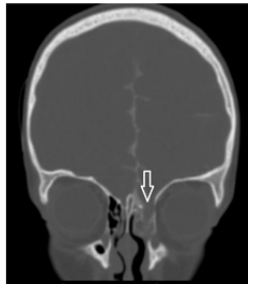

Пациентка Н., 6 лет, обратилась в Центр нейрохирургии с жалобами на периодические жидкие выделения из левой половины носа, нарушения обоняния, головные боли. По данным анамнеза в 5 лет получила травму в результате ДТП. Лечилась по месту жительства с диагнозом: сочетанная автодорожная травма: тяжелая лобно-лицевая травма. Ушиб головного мозга тяжелой степени. Паренхиматозно-субарахноидальное кровоизлияние. Вдавленный перелом лобной кости с переходом линии перелома на верхнеглазничные края орбит, корень носа, чешую височной кости справа, на переднюю черепную ямку. Перелом верхней челюсти справа. Гематосинус справа. По месту жительства проведена операция: декомпрессионная трепанация с удаление вдавленных отломков лобной кости. Спустя месяц пациентка выписана в удовлетворительном состоянии под амбулаторное наблюдение педиатра и невролога. Вскоре отметили появление жидких выделений из полости носа слева. Выполнено КТ, МРТ, на которых выявлено трансэтмоидальное менингоцеле, дефект основания черепа в области крыши решетчатого лабиринта слева (рис. 5).

Рис. 5: а — КТ, б — МРТ, фронтальная проекция, менингоцеле клеток решетчатого лабиринта слева. Стрелкой отмечен дефект крыши решетчатого лабиринта